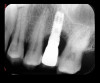

Fig 13. Radiograph depicting crestal bone loss around mandibular implants.

The first step in preventive strategies must be to perform a correct diagnosis of the peri-implant condition by accurately assessing the health of the peri-implant hard and soft tissues through periodontal probing and periapical radiographs at the time of definitive prosthetic installation. These measurements should be considered the baseline diagnosis and, therefore, represent a true starting point for evaluating the changes on the radiographic bone levels and probing pocket depths (PPD) at future recall appointments (Figure 1 and Figure 2).6 Although probing depth measurements of peri-implant tissues do not have the same diagnostic value as probing periodontal tissues, there is evidence that BOP is the most objective sign of peri-implant tissue inflammation; significant deepening of PPD compared with baseline measurements is also a sign of disease that indicates the need to perform a radiographic evaluation (Figure 3 through Figure 5).6,10,11

Following a similar paradigm of treating peri-implantitis the same way that periodontitis is regularly successfully treated, based on the mechanical removal of biofilms adhered to implant/abutment surfaces, different protocols of nonsurgical implant debridement using different mechanical, physical, and chemical mechanisms have been evaluated (Figure 12 through Figure 15). In general, the use of different protocols combining treatments aimed to decontaminate the implant surface (eg, mechanical, lasers) and control the infection process (eg, antiseptics, antibiotics) have shown clinical and significant improvements in the commonly used surrogate outcomes (mean reductions in PPD of around 1.2 mm and mean reductions in the scores of BOP of about 50%) but have not resulted in disease resolution18 or a high degree of predictablility.19 There is currently no specific nonsurgical therapy that has shown efficacy in the resolution of peri-implantitis, and the clinical improvements reported in the clinical studies were not sufficient for the arrest of the disease, leaving the standard of care in the treatment of peri-implantitis as surgical in most cases.20